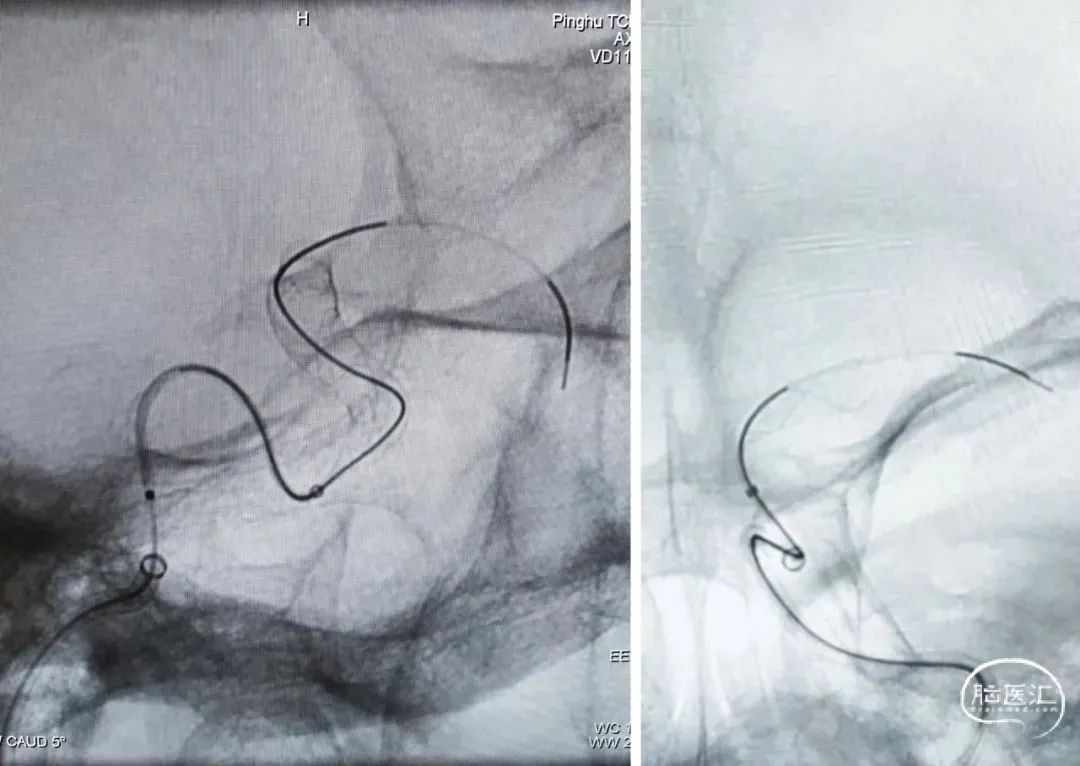

6F 70cm长鞘

6F 115cm中间导管

Synchro 0.014" 微导丝

XT-27微导管

泰杰 Nuva®血流导向密网支架 TJED-D-5.5-16

Echelon-10微导管

随后经支架微导管输送Nuva®血流导向密网支架 TJED-D-5.5-16到位,头端打开“V”字形后整体回撤系统至头端锚定位置,开始释放支架,过弯处推拉结合使支架更好打开,尾端减张缓慢释放。释放过程中分次造影并调整工作位,保证支架位置理想及打开良好。交换导丝简单按摩使支架在血管迂曲处更好贴壁。

1、该病例为大型宽颈动脉瘤,且瘤颈口位置朝向血流方向,受血流冲击影响较大,单纯弹簧圈栓塞复发风险高,密网支架具有血流导向作用,是优选方案。

2、该载瘤动脉血管迂曲,Nuva®血流导向密网支架镍钛合金材质顺应性好,过弯输送顺畅,自膨打开良好,贴壁完全,术中表现满意。